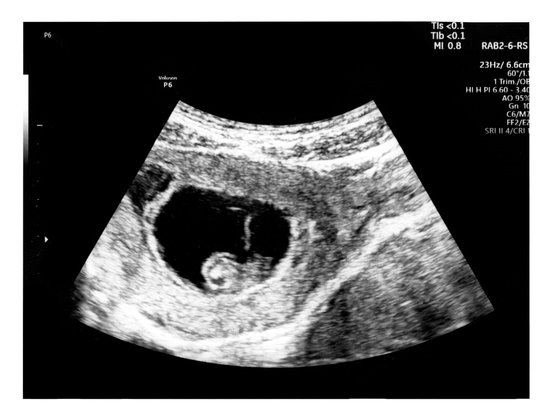

Wann ist ein Embryo wie groß? Und wie entwickelt sich das Baby im Bauch über das erste Trimester (SSW 1 bis SSW 12) hinweg? Hier findest du die Meilensteine. Wer es genauer wissen mag, klickt auf die jeweilige Woche, um noch mehr Details zu erfahren.

Die Embryo-Entwicklung im 1. Trimester als Tabelle im Überblick:

SSW | Entwicklung des Embryos | Durchschnitts-Größe Scheitel-Steiß-Länge | Durchschnitts-Gewicht |

Kopf und Rumpf werden in der 5. SSW angelegt. Das Herz fängt an zu schlagen. | 2 mm | - | |

Der Embryo ist in SSW 6 so groß wie eine Linse. Kopf, Hals und erste Gesichtszüge formen sich. | 4 mm | - | |

Der Embryo gleicht nun einer länglichen Bohne, die Nabelschnur bildet sich aus. Das Herz besteht in SSW 7 aus vier Kammern. | 5 mm | - | |

Hände und Füße nehmen in SSW 8 weiter Form an und die Hörorgane bilden sich aus. | 1,5 cm | - | |

Die Genitalien formen sich in SSW 9. | 1,7 - 2,2 cm | ||

Der Embryo wird zum Fötus. Das Baby kann in SSW 10 den Kopf bewegen. | 2,3 cm | < 4 g | |

Alle wichtigen Körperteile sind in SSW 11 angelegt. Die ersten Haare wachsen. | 4 cm | 8 g | |

Der Embryo gähnt, beginnt am Finger zu saugen und zu lächeln. Finger und Zehen trennen sich in SSW 12 voneinander. | 5 cm | 16 g |